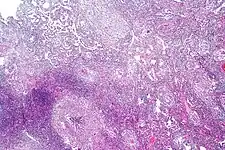

Pulmonary tuberculosis characterized by granulomatous inflammation with necrotizing epithelioid granulomas. Low power view. H&E stain.

Pulmonary tuberculosis featuring necrotizing granulomas, H&E stain.

Pulmonary tuberculosis featuring necrotizing granulomas, high power view, H&E stain.